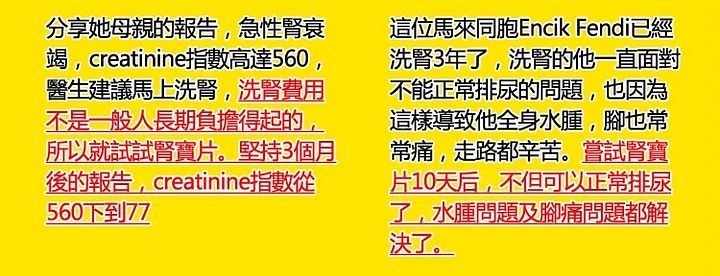

一位來自吉蘭丹的馬來同胞,她是忽然之間暴胖,媽媽就以為她吃太多也就沒理會,沒多久,她說腳痛,就不能走路啦,媽媽嚇壞了,趕緊帶她去看醫生,結果是【腎衰竭】,當時腎臟功能只剩下 30% ,醫生說過沒多久就必須洗腎,等時間罷了。能想像做母親的傷心嗎,孩子才 20 出頭,就要被這架儀器綁死一輩子!最後服用了兩個月的雲杉腎寶片,她女兒腎臟證實從 30% 功能回復至 70% 醫生說是奇蹟!真的是多虧了腎寶片拯救了女兒。

看看這個報告有很大的改善:

B4 AF 标准指数

Urea 19 8.8 ( 2.5 – 6.4 )

Creatinine 186 93 ( 53 – 88 )

CKD-EPI 32 74 ( >90 )

Urid Asid 0.69 0.33 ( 0.16 – 0.36 )

【 醫生嚴重警告他腎臟指數不樂觀 】- 服用後有很大的改善!他說非常有效!

這位是SetapakKL。美國雲杉腎寶片就是他的好朋友推薦他服用的,情況是這樣的:他長期尿酸,痛風,尿液渾濁,尿泡,糖尿病打胰島素,血壓偏高,就在近期體檢報告醫生嚴重警告他腎臟指數不樂觀,飲食一定要注意,阿民就問到有方法解決嗎,他不想要洗腎,醫生跟他說這樣子是可能可以拉長腎臟的壽命,西醫方面洗腎是唯一的結果【因為他健康問題太多了】。但是他經濟能力有限,也不想沒嘗試就放棄,洗腎的話,每個月的開銷他會更辛苦,最後在網路上購買了【美國雲杉腎寶片】,沒想到服用3個月後,尿酸,痛風,尿液渾濁通過好了,血壓也正常了,腎臟指數也樂觀了!